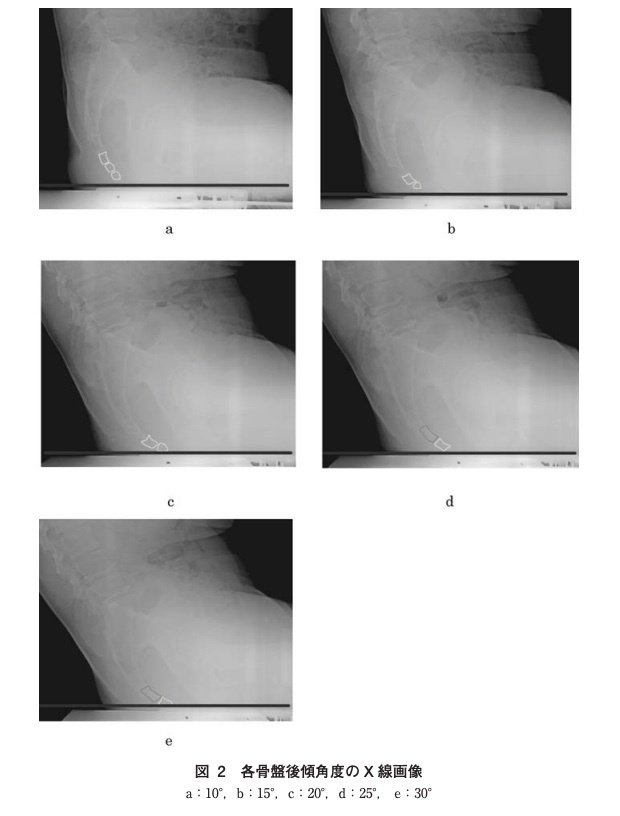

正常アライメント:仙尾骨角(立位/仰臥位、115.0 ± 10.6 mm/105.0 ± 12.5 mm)。尾骨の可動域は前後5〜20度とされます。

体位による変化:座位で体重がかかると尾骨は前屈し、立位では仙骨との角度が変化します。CT研究では、立位と仰臥位で仙尾骨角に有意な差があることが報告されています。